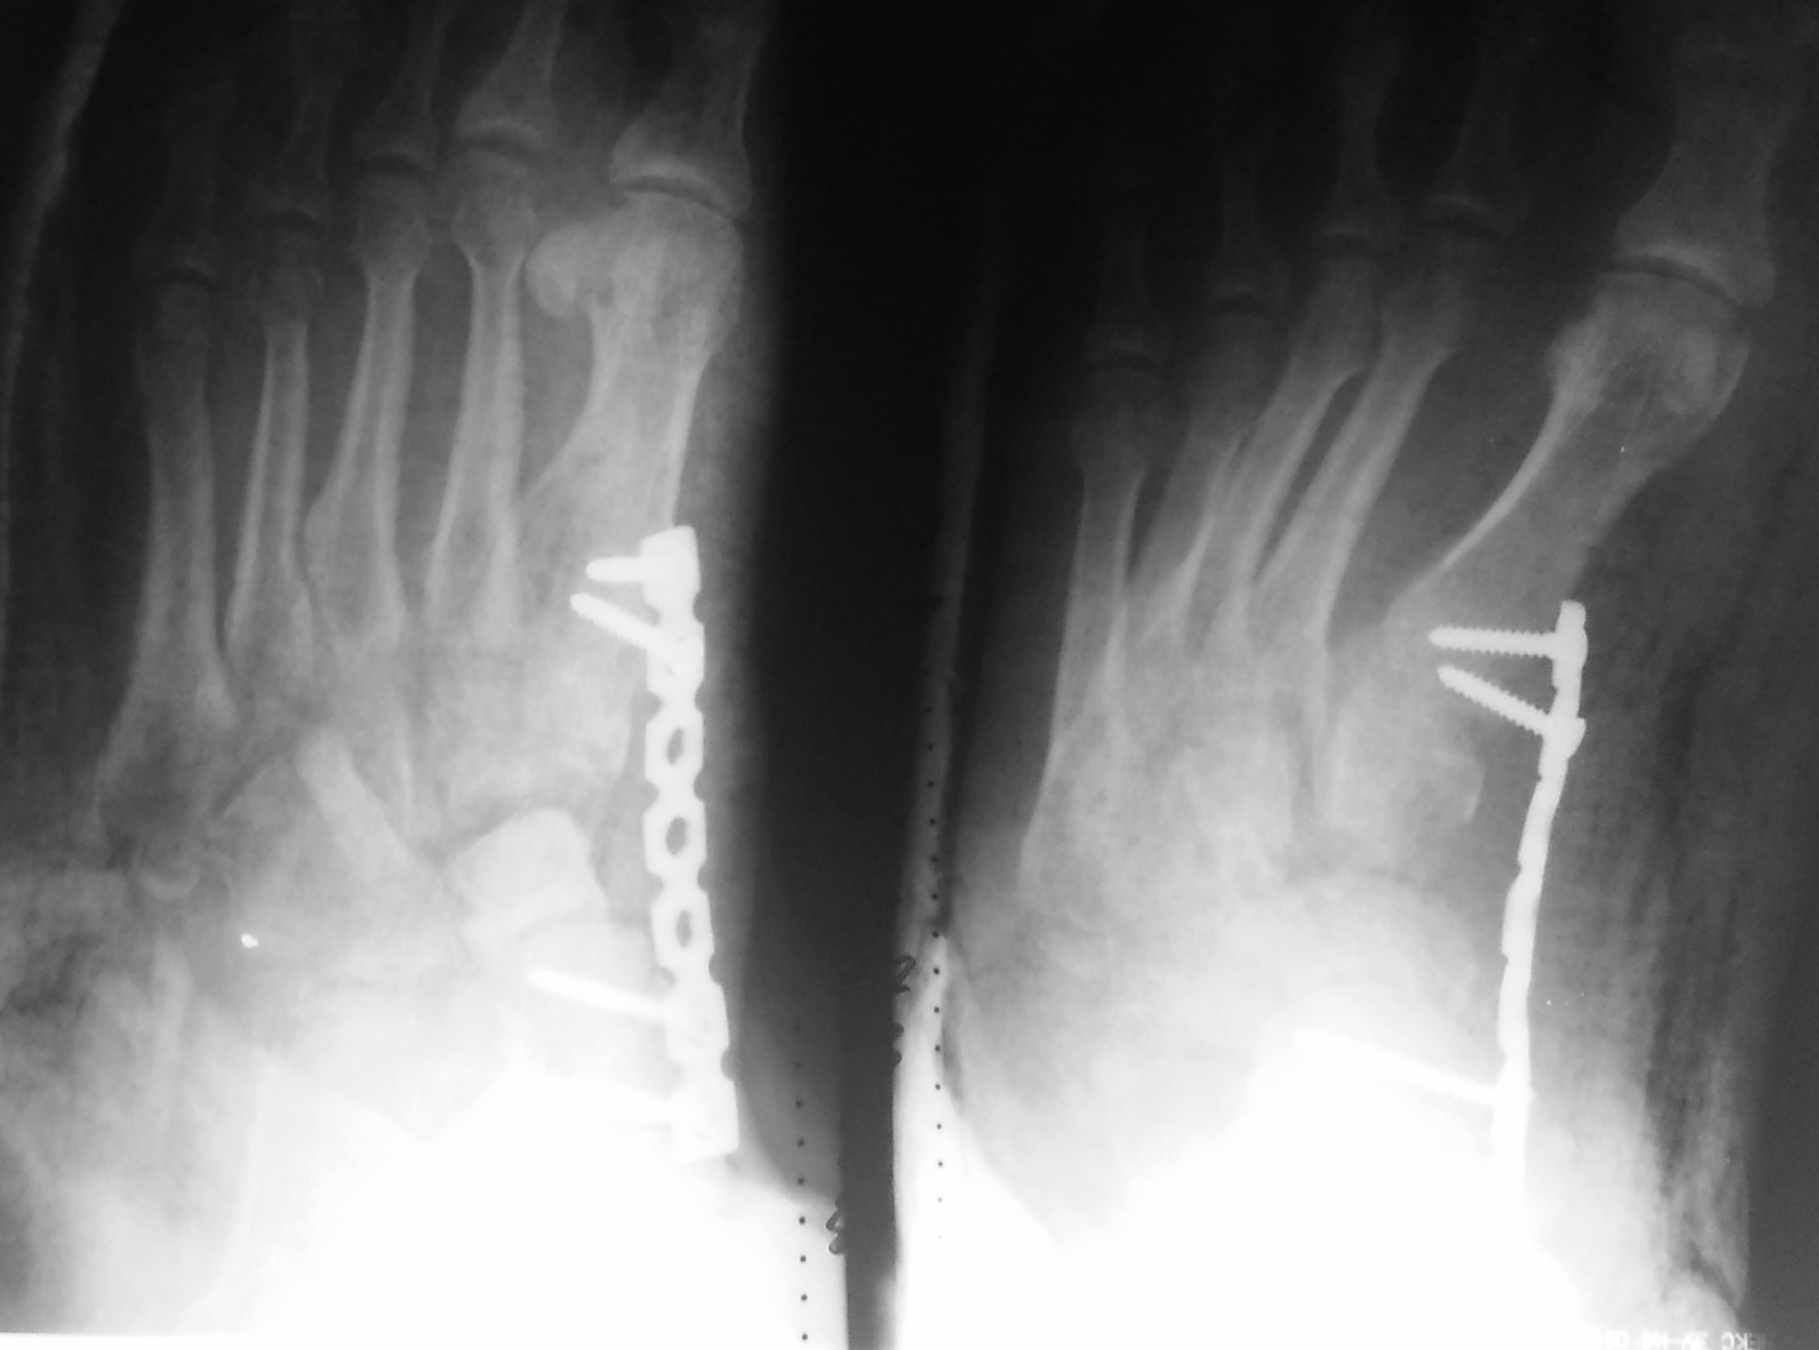

как-то так, извиняюсь за снимки, дистрактор все же пригодился, проблем с вправлением не было. На предыдущие вопросы, травма - по ноге проехал УАЗ, не курит, не злоупотребляет.

Здравствуйте! Может снимки повторить?

По тем, что есть вроде ситуация стала получше.

А почему такой выбран метод фиксации? вроде советовали спицами. И пластина как-то уж больно далеко от костей. Еще если можно фото после операции.